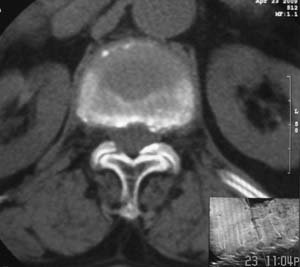

患者,女,72岁,胸背部疼痛3月余,无明显外伤史。曾应用局部封闭、非甾体类止痛药治疗效果不明显,近来疼痛缓解频感背困,平卧缓解,近日行ct检查发现胸12椎体病变,烦请同道发表意见,诊断什么?有何治疗经验!谢谢!!!

标绘图示:第十二胸椎级第一腰椎椎体楔形改变。ct扫描示:第十二胸椎椎体骨质结构紊乱,并可见一囊状低密度影,边缘可见硬化,椎体皮质完整。

考虑:第十二胸椎陈旧性骨折、许莫氏结节。